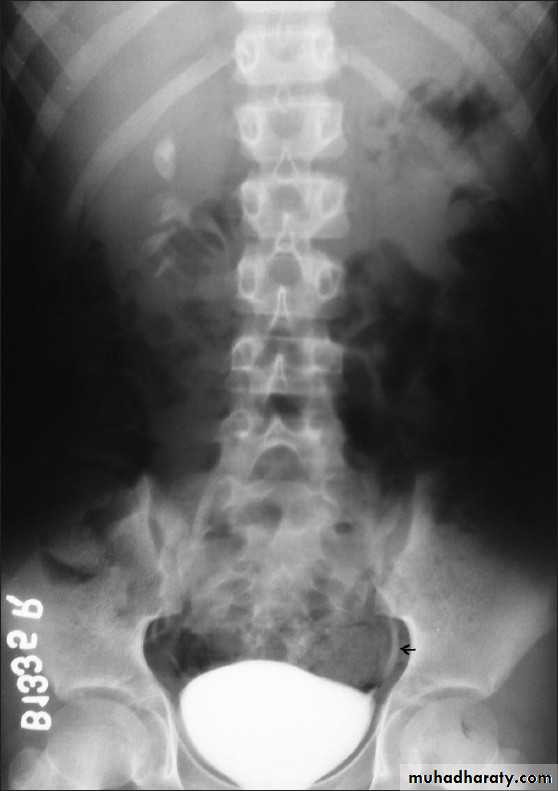

Ureterocele :

Congenital cystic dilatation of lower end of ureter ( intra-mural part) due to pin-hole meatus . May be simple or ectopic .

IVU :

- There is rounded or elliptical dilatation of lower end of ureter with thin lineal filling defect around it , resembling (cobra head appearance),

- Proximal dilatation of rest of ureter .

- In advanced cases hydronephrosis .

- In obstructed ureterocele , filling defect in the bladder